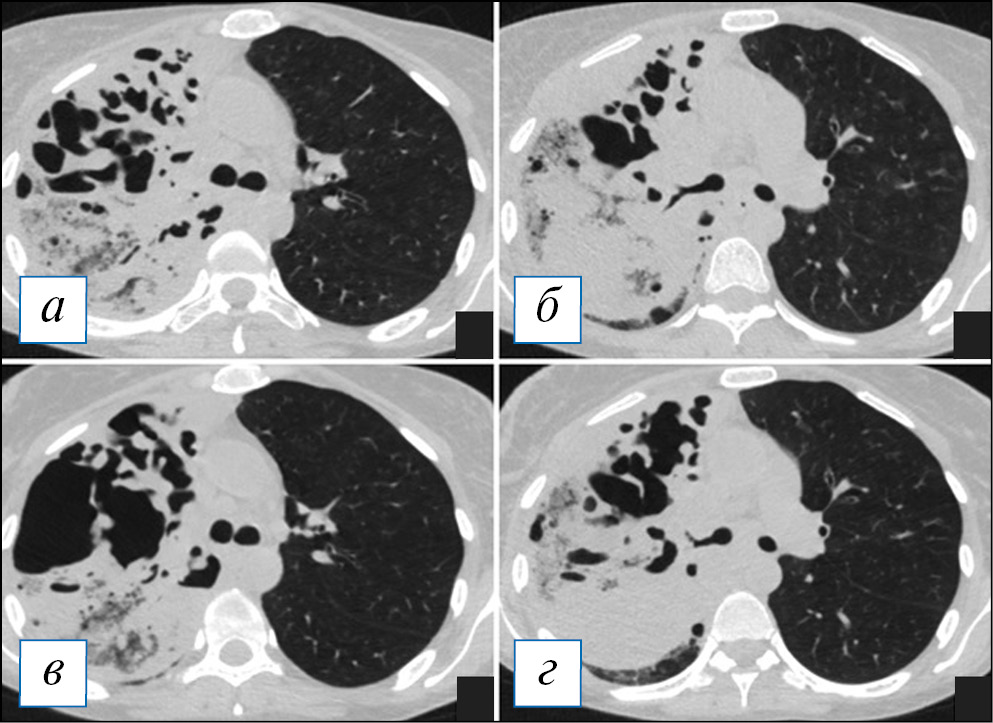

На КТ органов грудной клетки воспалительная инфильтрация легочной ткани при гангрене легкого не имеет четких границ и захватывает большое пространство — обычно больше одной доли, нередко все легкое (рис. 14). В начале процесса на КТ гангрена проявляется обширным участком консолидации (где частично прослеживаются просветы бронхов) или сочетанием консолидации с «матовым стеклом» (рис. 15). Далее, в динамике, на этом фоне появляются в большом количестве полости, обычно малого и среднего размера, в просвете которых обнаруживаются отдельно лежащие фрагменты легкого — секвестры (аваскулярные при контрастировании); могут быть видны сосудистые балки в виде тяжей, которые некротизируются обычно в последнюю очередь (рис. 16).

Рис. 14. Компьютерная томография органов грудной клетки в аксиальной (а–г) и сагиттальной (д) проекциях. Гангрена верхней доли левого легкого. Имеется тотальная инфильтрация верхней доли с наличием множественных полостей распада неправильной формы, а также фокусы инфильтрации в иных отделах легких. Небольшой выпот слева. [Изображения из архива авторов]. / Fig. 14. Axial (а–г) and sagittal (д) chest CT images. Gangrene of the upper lobe of the left lung. There is a total infiltration of the upper lobe with the presence of multiple irregular-shaped destructive cavities, as well as little areas of infiltration in other parts of the lungs. A small pleural effusion is seen on the left. [Images from the authors’ archive].

Рис. 15. Компьютерная томография органов грудной клетки в аксиальной (а–г) и сагиттальной (д) проекциях. Гангрена верхней и средней доли правого легкого в начальной стадии. Наблюдается тотальная инфильтрация долей в виде «матового стекла» и консолидации, на фоне которой имеются полости причудливой формы, склонные к слиянию. [Изображения из архива авторов]. / Fig. 15. Axial (а–г) and sagittal (д) chest CT images. Gangrene of the upper and middle lobes of the right lung at its initial stage. There is a total infiltration of the lobes in the form of ground glass opacity and consolidation, against which there are oddly shaped cavities that tend to merge. [Images from the authors’ archive].

Рис. 16. Компьютерная томография органов грудной клетки в аксиальной проекции от 14.09.2020 (а, б) и 22.09.2020 (в, г). Отрицательная динамика гангрены легкого. Наблюдается слияние мелких полостей в более крупные, неправильной формы; содержимое в полостях отсутствует. [Изображения из архива авторов]. / Fig. 16. Chest CT, axial projection from 14.09.2020 (а, б) and 22.09.2020 (в, г). Negative dynamics of lung gangrene. Small cavities confluence into larger ones, irregular shapes, the contents in the cavities are absent. [Images from the authors’ archive].